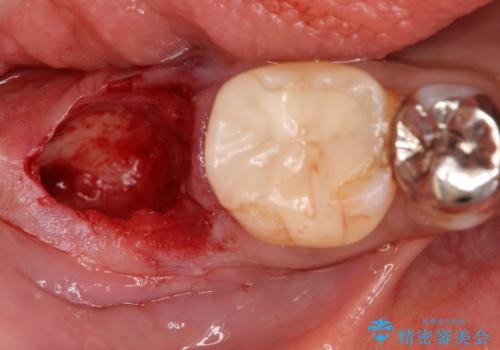

- 奥歯が痛いことを主訴に来院されました。

重度の歯周病により保存困難と診断し、抜歯後にインプラント治療を行いました。

抜歯後十分な骨の回復が認められず、単独の骨増生を行った後にインプラントを埋入しました。

インプラント埋入時に骨が足りない場合にはインプラント埋入前に骨増生を行います。また、インプラント周囲の角化歯肉が不足した場合は角化歯肉の移植も行うことがあります。